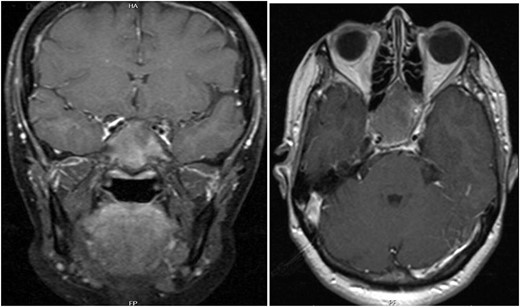

A 56-year-old female presented with a 1-year history of intermittent headaches, which had been increasing in severity and intensity over the last 2 months. The headache was mainly in the right parietal region, throbbing in nature and did not display diurnal variation. The severity of the headache was stated as 7–8 degrees on the Numerical Rating Pain Scale (NRPS; [6]). The pain was partially relieved with analgesia (acetominophen and ibuprofen). She also complained of mild right nasal congestion and intermittent mild otalgia. Physical examination was normal apart from nasal septal deviation. Computed tomography (CT) of the paranasal sinuses showed expansion of the sphenoid bone demonstrating diffuse ground-glass matrix and sclerosis obliterating the sphenoid sinus cavity (Fig. 1). Magnetic resonance imaging (MRI) was highly suggestive of fibrous dysplasia of the sphenoid bone, which appeared as expanded mass with dark T2 signal and T1 hypointense signal (Figs 2 and 3). Near-total excisional biopsy was performed using endoscopic transeptal approach to sphenoid sinuses. Histopathological examination of several pieces of greyish tan and brown bony tissue measuring 3.5 × 2.5 × 1.7 cm. showed branching irregular trabeculae of woven bone with intervening hypocellular fibrous stroma, consistent with a diagnosis of FD (Fig. 4). The patient’s headaches improved greatly following surgery. Two years post-op she reports infrequent headache with a severity of 2 on NRPS.

Coronal T1 image showing the expansion of the clivus with heterogeneous predominantly low T1 signal. Axial flair images showing the anteroposterior (AP) extension of the mass lesion with obliteration of the sphenoid sinuses. The cavernous portions of both internal carotid arteries (ICAs) have signal void intensity suggesting patency.

T1 axial and coronal post-contrast images show some heterogeneous enhancement compared to pre contrast images.